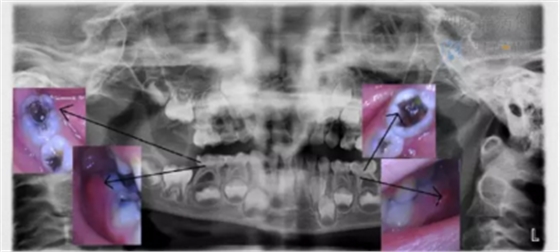

小科:不一定,但大部分情況都是。因為牙疼大部分是齲壞深入到牙本質(zhì)引發(fā)的。也要看牙齒具體情況,如果拍片子檢查后,齲壞已經(jīng)滲入牙本質(zhì)深層,引發(fā)了牙髓或根尖炎癥,就是牙齒內(nèi)部出現(xiàn)了炎癥,那就需要做根管治療了。

醫(yī)生不是掃描儀,也沒有透視眼,為了解患牙的牙根形態(tài)、走向、長度及根尖周有無病變及病變大小,醫(yī)生常常要求患牙在根管治療術(shù)前,術(shù)中和術(shù)后分別拍X線片,以幫助診療。